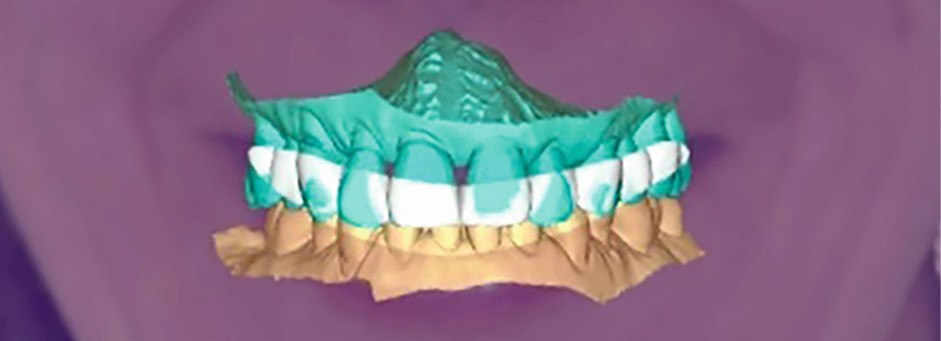

L’empreinte optique, les photographies et le CBCT ont permis une fusion précise des données numériques pour planifier les axes et positions implantaires en fonction du projet prothétique final (fig. 3, 4).

Cette planification a ainsi intégré la future ligne d’émergence et la gestion anticipée des tissus mous [2].